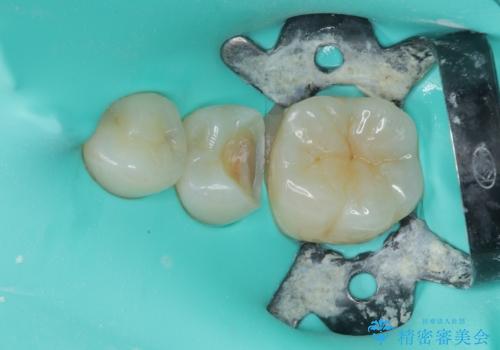

拡大鏡視野下で虫歯の除去を行い、セラミックインレーに適した形に整えました。

歯と歯茎の間に圧排糸と言われる糸を入れてシリコーン印象材にて精密な型どりをしました。

セラミックインレーの装着時には、唾液の侵入を防ぐために、ラバーダム防湿を行いました。